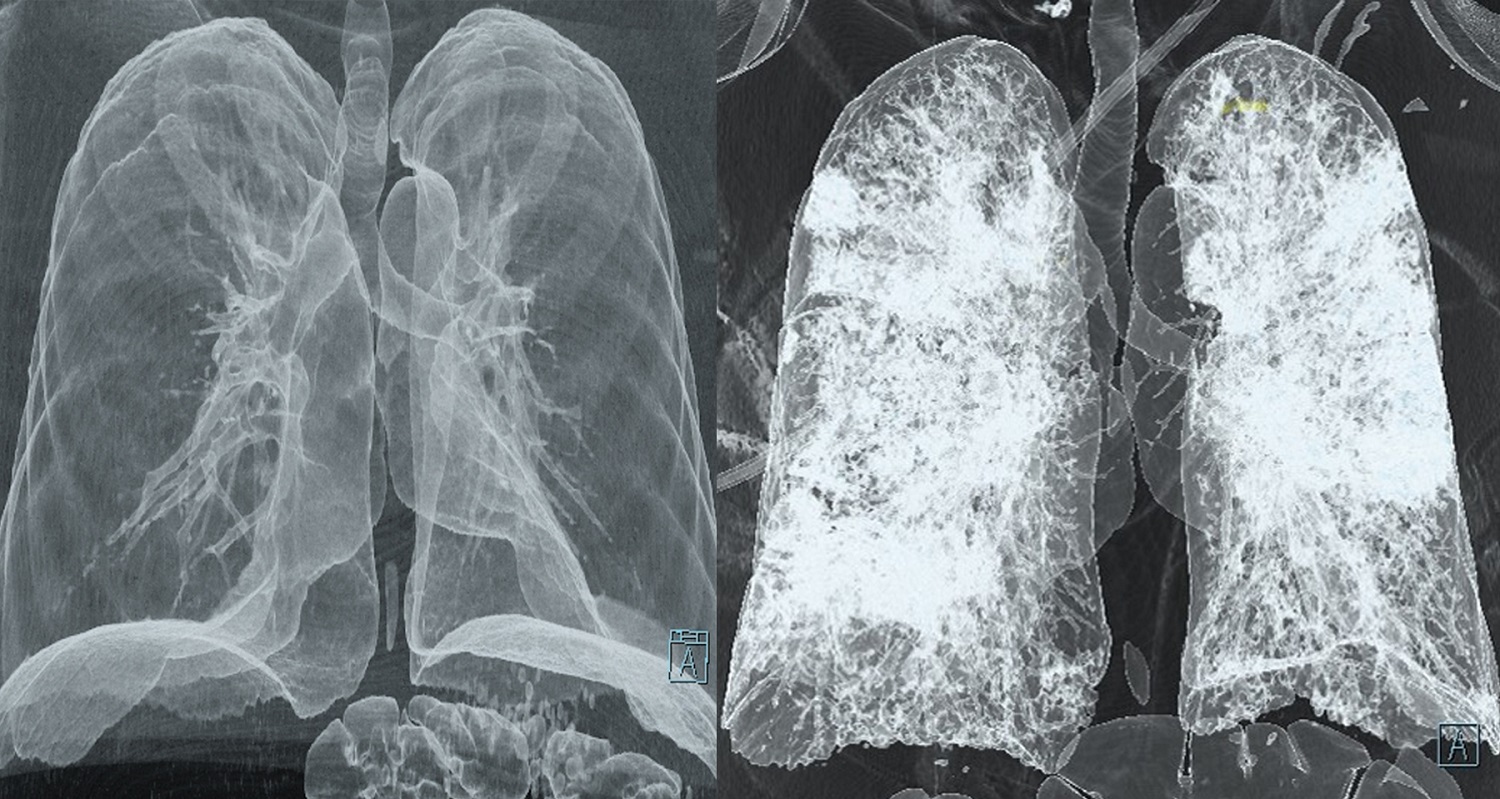

CT scans of healthy lungs vs. lungs attacked by COVID-19

CT scans reveal the damage COVID-19 can wreak (right) on typically healthy lungs (left). Vancouver Coastal Health

While the slate of COVID-19 symptoms is long and mysterious, many patients seem to come down with pneumonia or worse, go into respiratory failure. Studies on some of these deadly cases show that the virus makes a beeline for lung tissue, causing the cells to grow, inflame, and even clot. Now, patients hospitalized for the virus automatically get a CT scan as part of their diagnostic test. Medical researchers in Canada and elsewhere are also using artificial intelligence to detect more subtle signs of disease in the lungs.